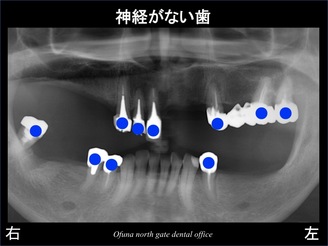

しかし、この症例の患者様の場合、神経がない歯が非常に多く ブリッジが最適な状態ではありませんでした。

神経がない歯は以下のレントゲンの青丸になります。

神経のない歯が非常に多いのが分かります。

いつも説明していますが、神経のない歯は脆く さまざまなトラブルが起こりやすい 状態です。

今回 下顎右側奥歯の欠損部には、神経のない歯によるブリッジを選択しました。

もちろん 神経のない歯同士でのブリッジは、リスクが高い治療にはなります。

しかし、欠損部全てにインプラント治療を行うことは、治療費の点から無理なことでした。